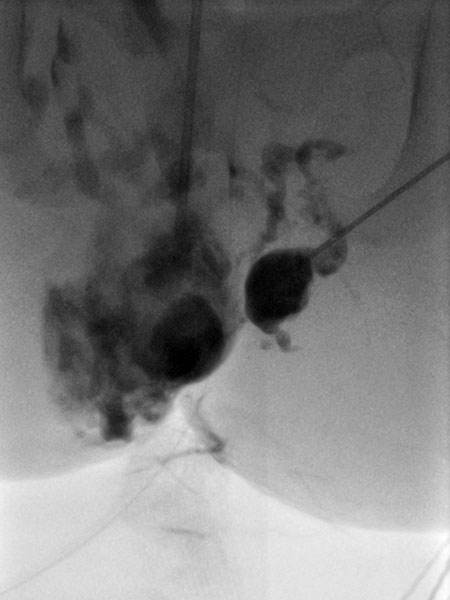

After confirmation of the diagnosis, bleomycin electrosclerotherapy was performed. For this purpose, the venous malformation was first punctured on both sides with a needle under ultrasound guidance and injected with contrast medium. Good needle placement, no major drainage veins were found.

A total of 0.75 mg bleomycin (diluted one to three in contrast medium) was now injected directly into the venous malformation via the two horizontal needles. Subsequently, a total of 11 applications of reversible electroporation with finger electrode with 15 mm active needle length were performed on both sides.